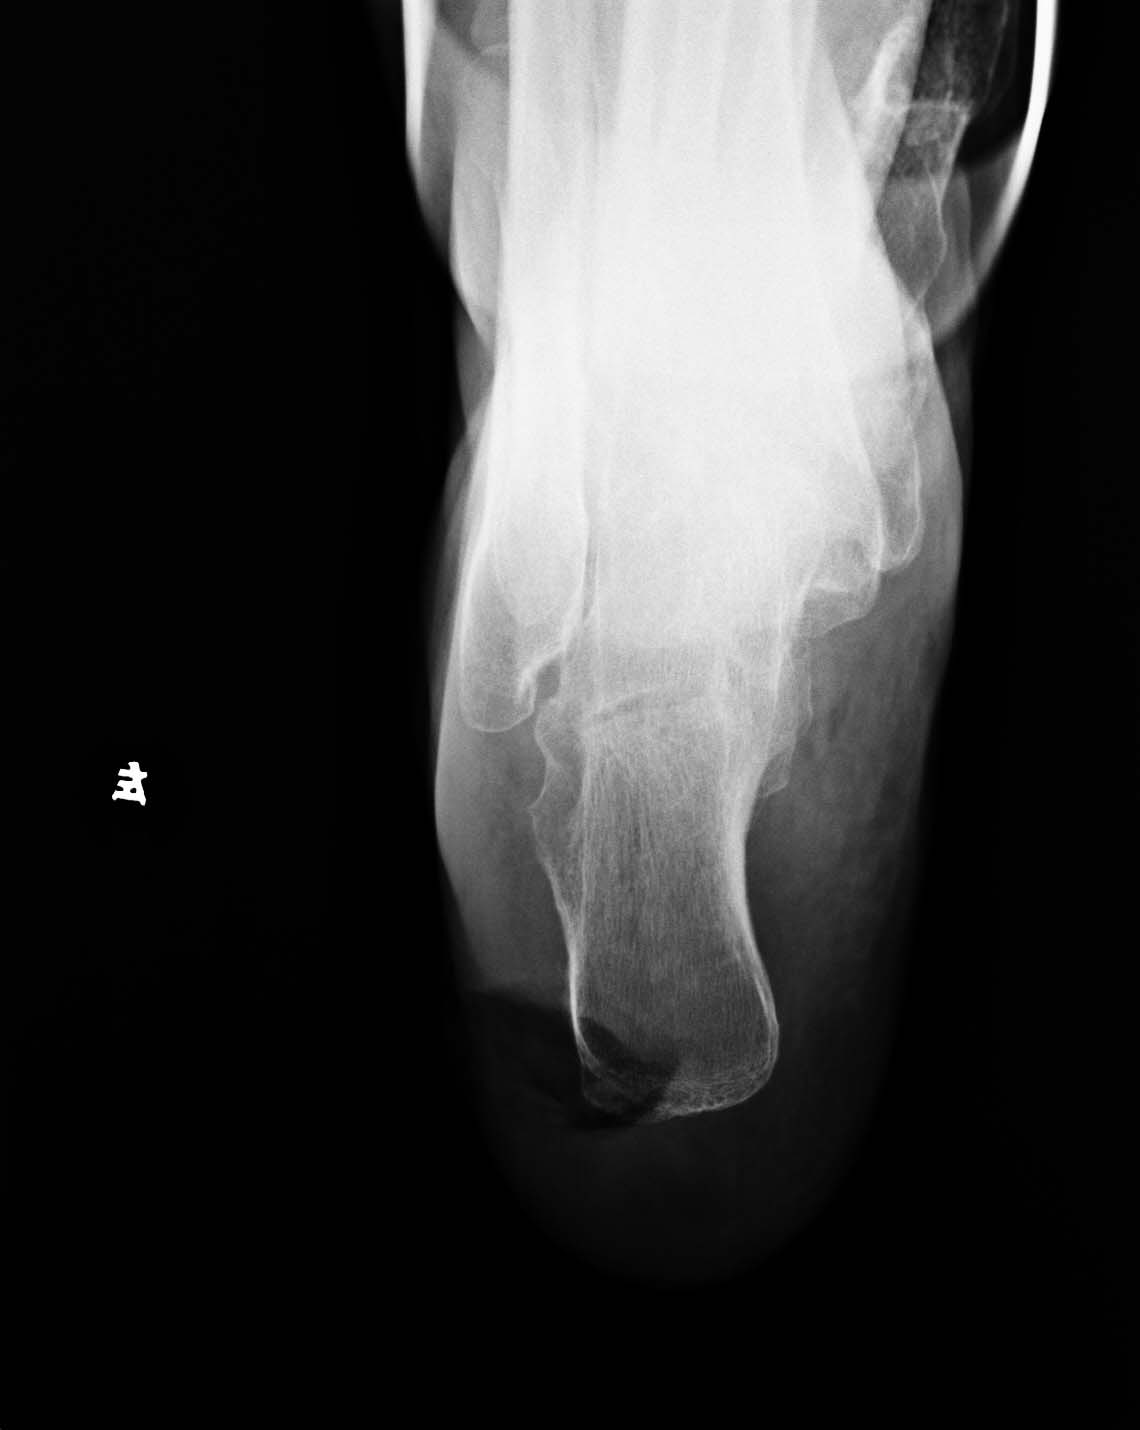

女,65岁,跟部软组织溃疡已二年,现跟骨下方见骨膜反应,x线报告上如何诊断。

1、左跟部软组织溃疡

2、左跟骨下缘骨膜炎,建议随诊

跟部软组织感染、窦道形成并跟骨骨膜炎

1、左跟部局限性软组织缺失

2、左跟骨骨膜炎,建议密切观察,除外跟骨骨髓炎

足跟部软组织感染、窦道形成并跟骨骨膜炎。